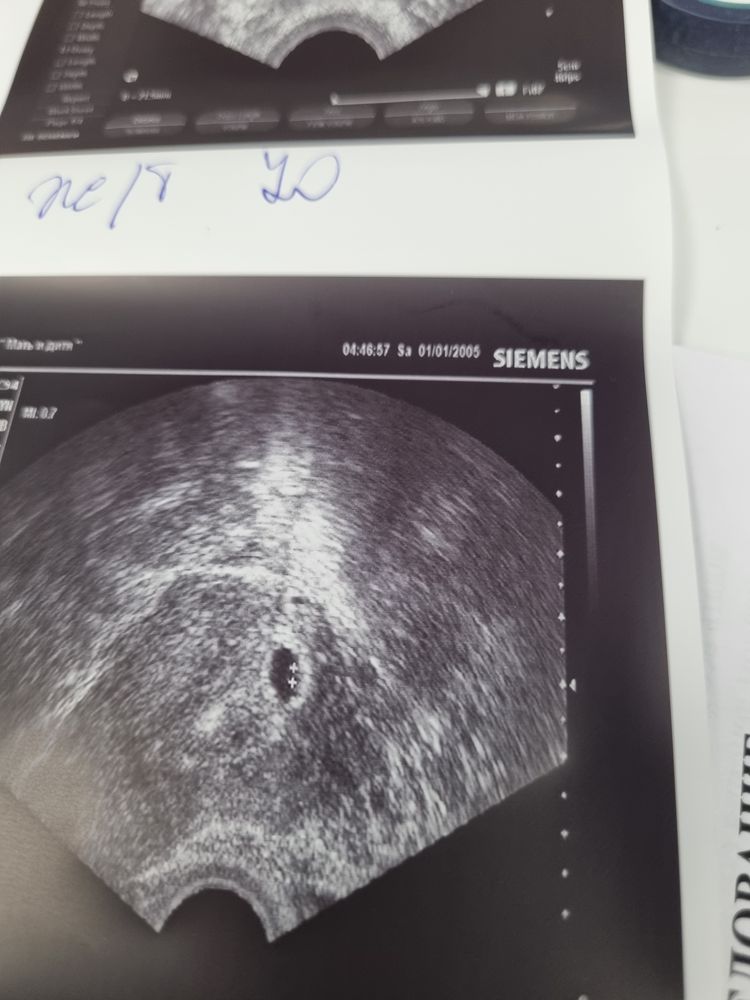

23 дпп узи